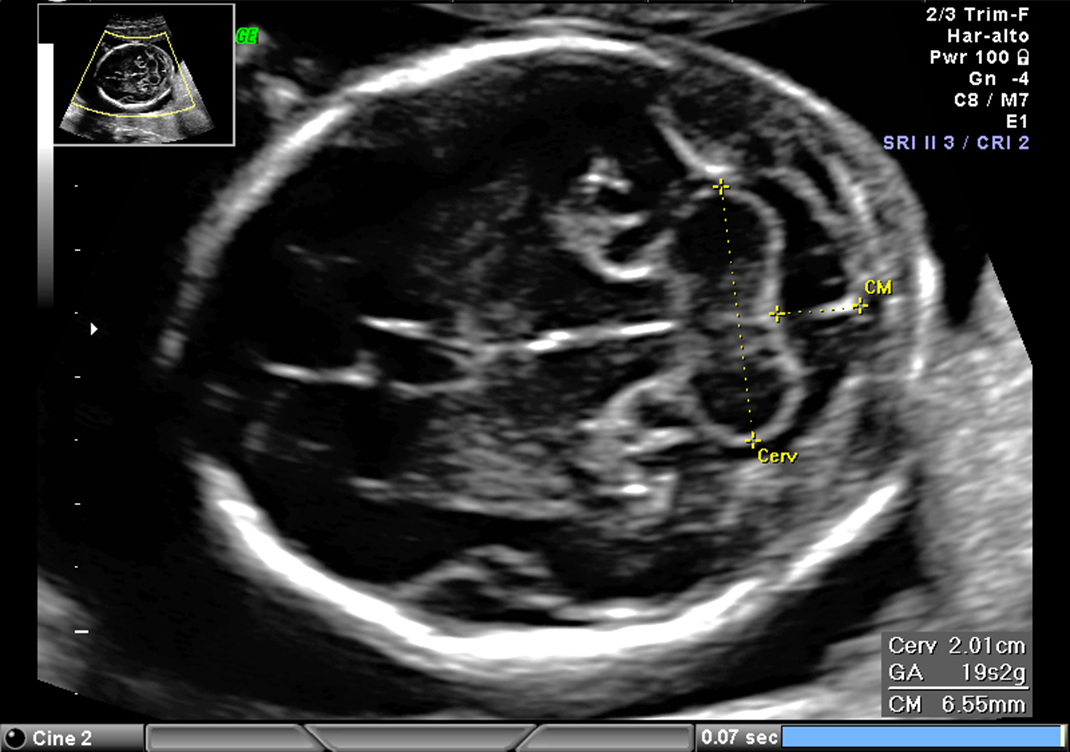

lateral ventricles should not exceed

1-1.1 cm

calipers of choroid plexus and lateral ventricles

inner to inner

measure _____ portion of lateral ventricle through the most _____ portion of choroid plexus

posterior, posterior

cisterna magna should be less than

1cm